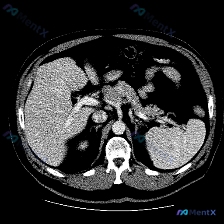

今天看到一份很有意思的影像资料,提问直接指向“脾脏特异性异常”,但仔细读完图像和分析,发现里面藏着一个很典型的临床思维陷阱,整理一下思路和大家分享。 先看这张CT的客观发现 这是一张腹部CT横断面软组织窗图像: 1. 脾脏:形态可见,密度均匀,没有看到明确的增大,也没有局灶性的高低密度病变; 2....

整理了一份有点「反转」的影像读片资料,感觉挺考验临床思维的,分享出来一起理理思路。 --- 一、影像基本信息 这是一张腹部CT横断面软组织窗图像,预设的观察焦点是「脾脏病变」。 二、结构化读片所见(客观描述) 按照读片常规扫了一遍全腹: 1. 肝脏、胆囊、胰腺:形态、大小、密度都正常,轮廓光滑,胰周...

今天看到一个很有意思的影像分析场景,整理一下思路和大家分享。 --- 病例背景 用户提供了一张腹部CT横断面(软组织窗),并直接询问:“图片中可见的特殊异常是什么?脾脏病变”。 影像核心表现 我先按标准流程梳理了这张CT的关键信息: 1. 脾脏:大小、形态正常,脾实质密度均匀,明确未见占位、梗死或异...